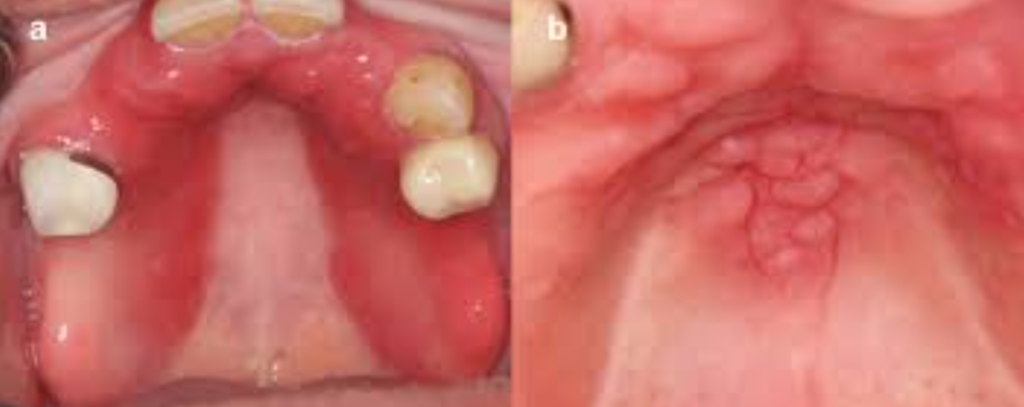

La stomatite sous-prothétique

C’est une lésion de la muqueuse buccale fréquente provoquée par les prothèses dentaires dans les populations âgées. La colonisation par des levures sur l’intrados de la prothèse en est l’origine principale. Elle est fortement liée à l’hygiène bucco-dentaire.

Autres facteurs incriminés :

- Prothèse non déposée la nuit

- Trempage nocturne non respecté

- Utilisation de produits de trempage inappropriés

L’hyperplasie fibro-épithéliale

Il s’agit d’une lésion fréquente chez le sujet porteur de prothèses amovibles anciennes et inadaptées en raison de la résorption osseuse liée au vieillissement. Les mouvements répétés d’aspiration entraînent une évagination de la muqueuse, réalisant une hyperplasie fibreuse en forme de « feuillets de livre ». L’excision chirurgicale avec contrôle histopathologique et la réadaptation des prothèses constituent la conduite à tenir.